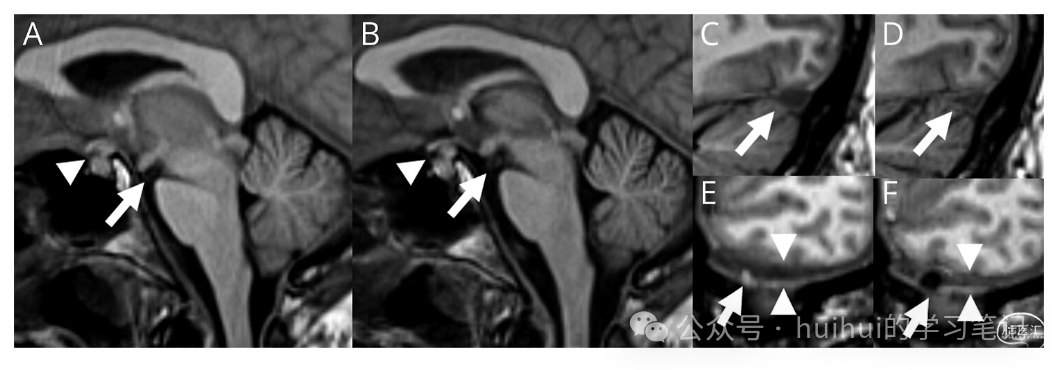

一名 65 岁男性出现 3 个月的每日直立性头痛和顽固性恶心,无外伤或出血素质。检查注意到右面部下垂波动,直立时唤醒减少,平躺时改善。头部 CT 显示双侧硬膜下积液,MRI 显示自发性颅内低血压 (SIH) 的柱头,包括脑下垂(图 1 和 2)。脊柱 MRI 显示小的神经周围憩室,无硬膜外液体。侧卧位动态 CT 脊髓造影1显示左侧 T8 CSF 静脉瘘(图 1C)。瘘管经静脉栓塞术(图 1D)导致第一天头痛、恶心和意识水平得到改善,位置神经功能缺损在 4 天内完全消退。48 小时重复脑部 MRI 显示脑下垂、静脉扩张和蛛网膜颗粒新出现明显改善(图 2)。治疗后数月通常可以看到 MRI SIH 结果的改善;然而,尚未很好地描述 48 小时内的快速改善。